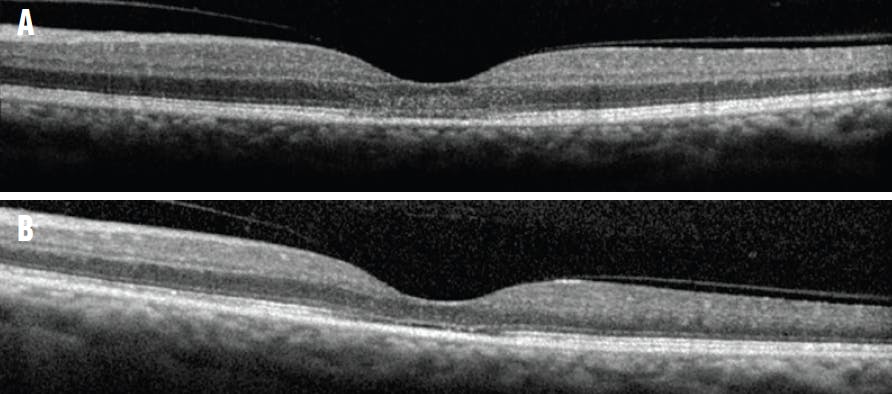

<p>Figure 1. OCT imaging of mild TPSS demonstrates mild blurring of the IS/OS and ELM at presentation (A) and improvement after 1 month (B).</p>

Figure 1. OCT imaging of mild TPSS demonstrates mild blurring of the IS/OS and ELM at presentation (A) and improvement after 1 month (B).

Varying degrees of outer retinal thinning on OCT were identified in eyes with TPSS. Every case demonstrated disruption or loss of the external limiting membrane (ELM) and inner segment/outer segment (IS/OS), with greater loss typically correlating with worse TPSS grade and visual acuity (Figure 1). Outer retinal disruption improved gradually over time in each patient (Figure 2). Disruption of the retinal pigment epithelium (RPE) was variable but was typically associated with more severe retinal thinning and worse visual outcomes (Figure 3). Twenty-eight eyes demonstrated involvement of the RPE, with the majority experiencing a final BCVA of 20/200 or worse (n = 21). Only one case of mild TPSS involved the RPE with a final BCVA 20/40.